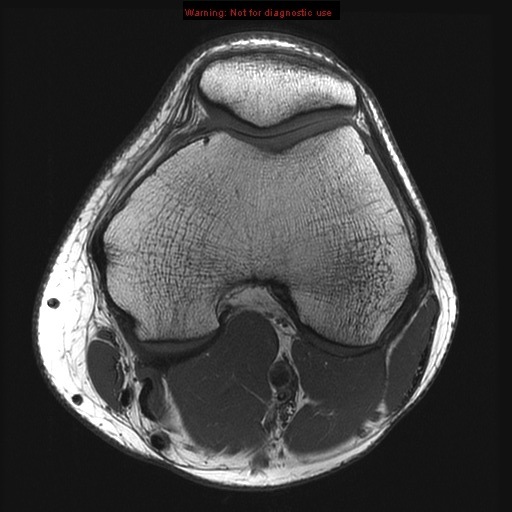

Stanford MSK MRI Atlas

posterior cruciate ligament

anterior cruciate ligament

meniscofemoral ligament

ligament of wrisberg

iliotibial tract anterior cruciate ligament

transverse ligament

ligament of humphrey patella